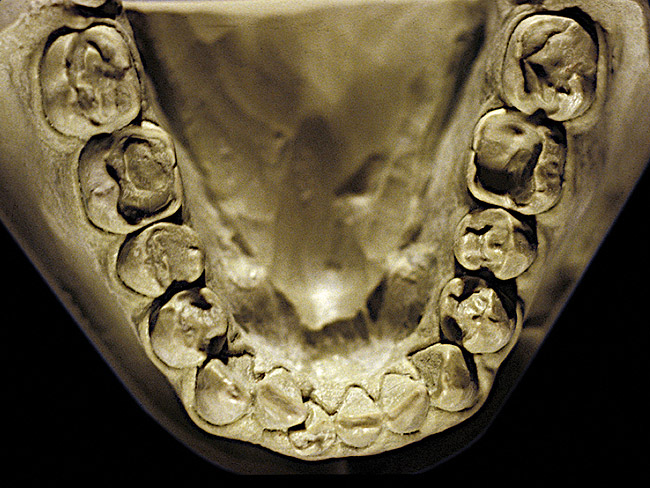

The patient shown in Figure 3 and Figure 4 exhibited severe NCLTS from bruxism. Examination of the casts indicated that the NCLTS was progressively greater toward the anterior teeth. Cupping and cratering was not present because there was no secondary cause. Figure 5 and Figure 6 detail another bruxism patient, but to a lesser degree and one with cupping/cratering caused by toothpaste. The cups or craters were not caused from bruxism because the teeth could not touch the bottom of the invaginations. In both featured patients, upon hand-articulating the casts, the NCLTS facets matched up and the diagnosis of bruxism was confirmed.

Figure 2  Advanced NCLTS from bruxism, mandibular arch.

Figure 2

Figure 4  Advanced NCLTS from bruxism, maxillary arch.

Figure 4